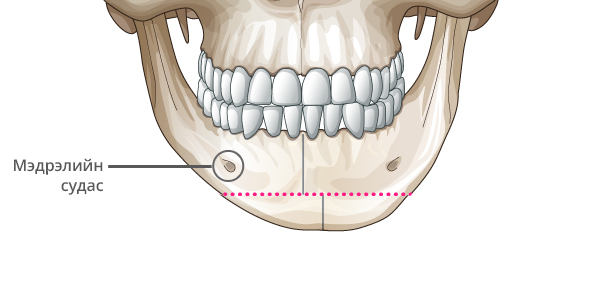

Step 1

Мэдрэлийн судсыг тойруулж, эрүүний төгсгөлд T зүсэлт хийнэ.